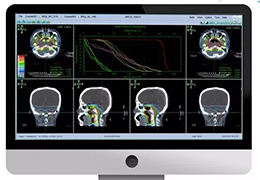

人工智能不再是一项抽象的承诺。Eclipse 引擎为 ImageView 软件提供支持,将 AI 付诸于无可争议的行动,即通过成像智能、工作流智能和分析智能推动产生具体、可衡量的结果。

成像智能。

Eclipse 成像智能功能提供强大的处理能力和最佳质量的影像,同时减少质量错误并提高剂量效率。

凭借 AI、专有算法和先进的影像处理能力,提供出色的影像质量和无与伦比的诊断信心。